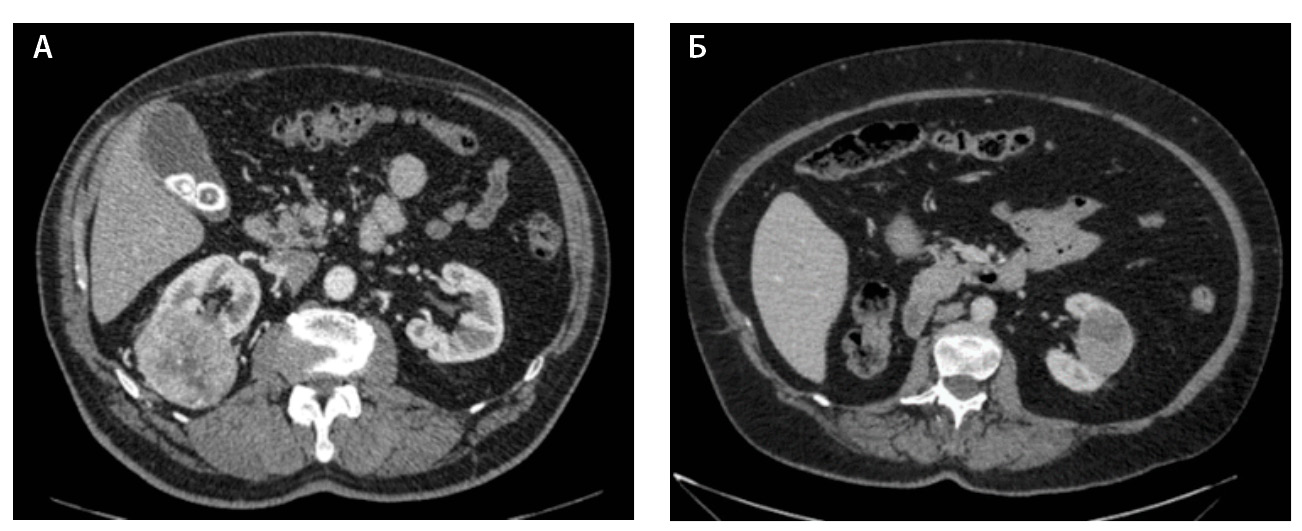

Компьютерная томография (КТ) с внутривенным контрастным усилением широко используется как метод диагностики и первичного стадирования скПКР. В настоящее время наиболее значимыми характеристиками опухоли для предоперационного стадирования и планирования хирургического лечения скПКР признаны расположение, размер опухоли и признаки ее инвазивного роста [3–6], а структура и характер контрастирования позволяют дифференцировать типы ПКР, но ни один из этих показателей не дает возможности достоверно прогнозировать степень дифференцировки опухоли. Структура скПКР любой степени дифференцировки, как правило, гетерогенная с наличием солидного и кистозного компонентов. Признаки инвазивного роста опухоли, наличие метастазов позволяют предположить низкую степень дифференцировки опухоли, однако не являются достоверными признаками. Как видно на рис. 1, скПКР разной степени дифференцировки по данным КТ выглядят практически идентично: в обоих случаях визуализируется опухолевый тромб в почечной вене с распространением в просвет нижней полой вены. Такие характеристики, как размер опухоли, пофазное накопление контрастного вещества и градиент накопления контрастного вещества при КТ-исследовании, также не являются строго специфичными для разных степеней дифференцировки скПКР (рис. 2).

Рис. 2. Светлоклеточный почечно-клеточный рак. А – Grade 1 (данные компьютерной томографии пациента С.), кортико-медуллярная фаза исследования: трансмуральная опухоль правой почки размером 6,6 см, с четкими и ровными контурами, прилежит к синусу почки, опухоль имеет солидно-кистозное строение, солидный компонент опухоли накапливает контрастное вещество (КВ) менее интенсивно, чем кортикальный слой почки, градиент накопления КВ солидным компонентом опухоли 50–60 HU. Б – Grade 4 (данные компьютерной томографии пациентки Щ.), кортико-медуллярная фаза исследования: трансмуральная опухоль левой почки размером 5,2 см, с четкими и ровными контурами, прилежит к синусу почки, опухоль имеет солидно-кистозное строение, солидный компонент опухоли накапливает КВ менее интенсивно, чем кортикальный слой почки, градиент накопления КВ солидным компонентом опухоли 45–60 HU